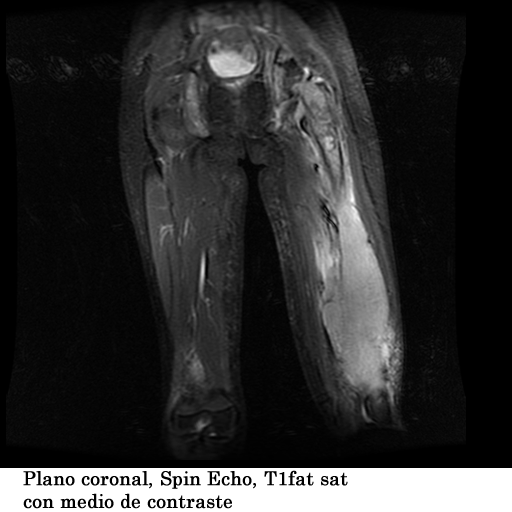

Paciente femenina, de 18 años de edad, con masa visible y palpable a nivel del tercio medio e inferior del fémur izquierdo, con un tiempo de evolución de 1 año, refiere dolor y limitación al movimiento.

TECNICA EMPLEADA

Se coloco al paciente en decúbito supino, utilizando una bobina fase array, haciendo adquisiciones en los planos axial, sagital y coronal, secuencias, spin echo, eco de gradiente e hibridas, potenciadas a T1, T2 y DP, secuencias Steer, y se obtuvieron imágenes con saturación de grasa.

HALLAZGOS IMAGENOLOGICOS

1. Edema de tejidos blandos que infiltra los músculos del muslo en su tercio medio y distal

2. Fractura patológica de tercio proximal de la diáfisis femoral izquierda

3. Engrosamiento del periostio del tercio medio y distal de la diáfisis femoral izquierda